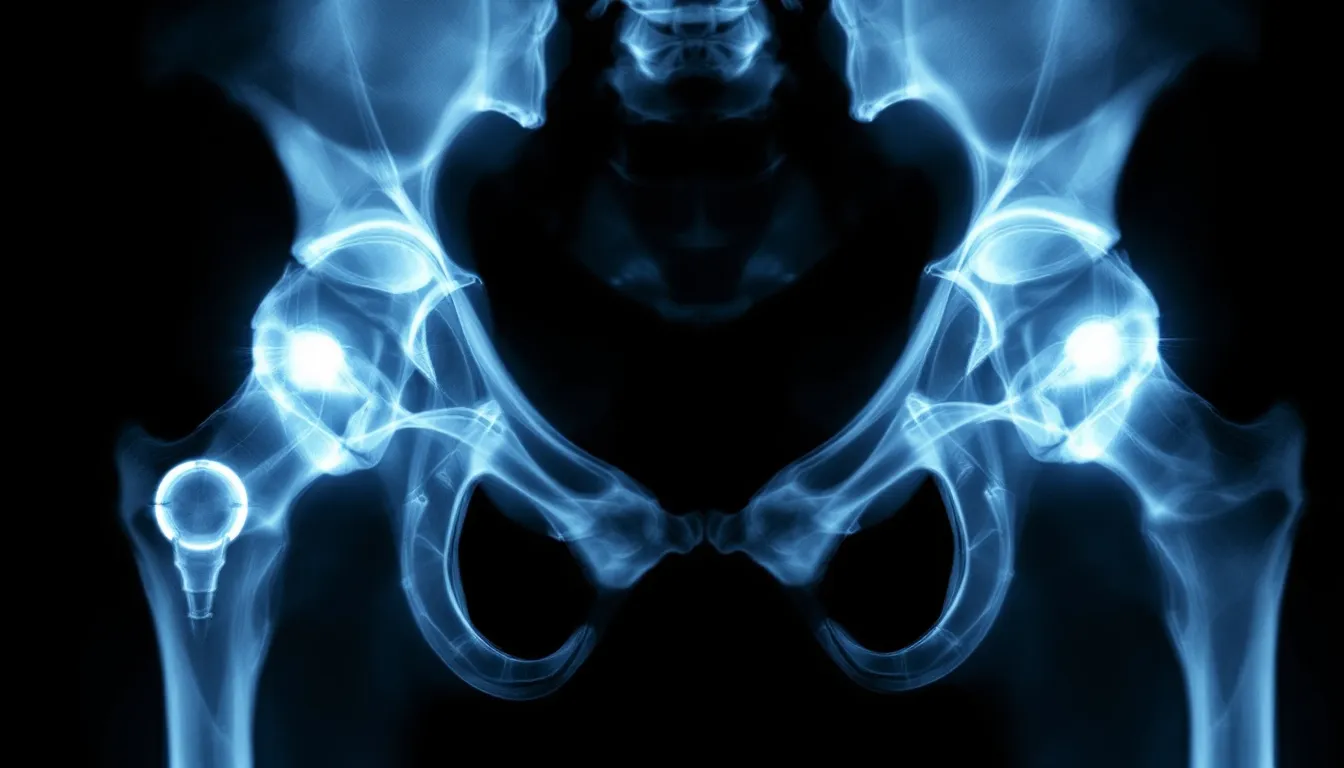

Total hip replacement provides the most comprehensive solution for dogs with severe hip dysplasia. This procedure replaces both the femoral head and acetabulum with metal and plastic implants, essentially creating a new hip joint. Costs typically range from $3,000 to $7,000 per hip, but success rates exceed 90% in properly selected candidates.

An X-ray image displays total hip replacement implants in a dog, highlighting the artificial components within the hip joint, which is a common surgical intervention to treat hip dysplasia in dogs, especially in large breed dogs. The image illustrates the ball and socket joint, essential for understanding the surgical procedure and its role in alleviating joint pain associated with canine hip dysplasia.

Femoral head ostectomy (FHO) creates a false joint by removing the femoral head entirely. While less expensive than total hip replacement, this procedure works best in smaller dogs where the surrounding muscles can adequately support the modified joint structure. Larger dogs may experience persistent lameness following FHO.

Surgical intervention timing is crucial for optimal outcomes. Procedures like TPO must be performed before arthritis develops, while total hip replacement works best after skeletal maturity. A board certified veterinary surgeon can help determine the most appropriate surgical option based on individual patient factors.